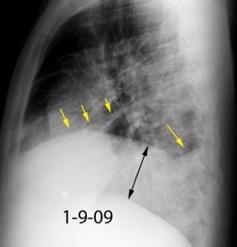

En relación con trasudados tabicados. Insuficiencia cardiaca

Hipoalbuminemia

Cirrosis / Fallo renal.

Operado aneurisma (prótesis). Líquido tabicado en cisuras

Fernandes de Paula MC et al. Focal pleural tumorlike conditions: Nodules and masses beyond mesotheliomas and metastasis. Respiratory Medicine 2015.

Derrame pleural “encapsulado”

“Tumor fantasma”

Asociado a fallo cardiaco. ( “Pleuritis adhesiva”). Buch KP. Chest. 2000